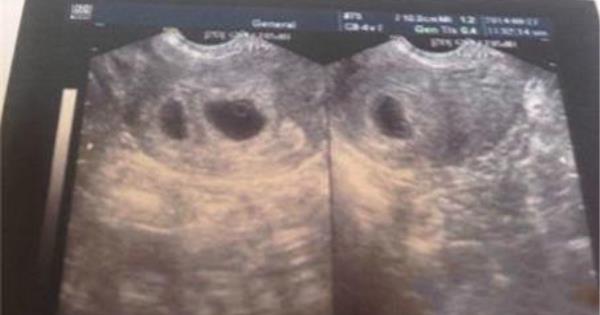

30歲的蔣蔣懷孕10周時到醫院產檢,醫生告訴她,可能是雙胞胎。半個月後去複查,檢查結果為“雙胎囊雙原始心管搏動”,是雙卵雙胎。 這可把蔣蔣樂壞了。雖然早知道家族裡有雙胞胎基因,但是真的確定的時候還是覺得很幸運。 然而,幸福太短暫,僅僅持續了一個月。  一個月後,當蔣蔣再去產檢時,醫生對照此前的B超圖像發現,兩個寶寶居然是在一個胎囊裡,情況不太好,故建議她重新檢查。而重照B超的結果讓林女士嚇了一跳:只有一個胎兒,另一個“不翼而飛”了。 B超檢查沒問題,也沒有流產跡象,寶寶到底去哪兒了? 醫生表示,蔣蔣的這種情況在臨床中並不罕見,和自然流產一樣,是胎兒在宮內停止發育所致。